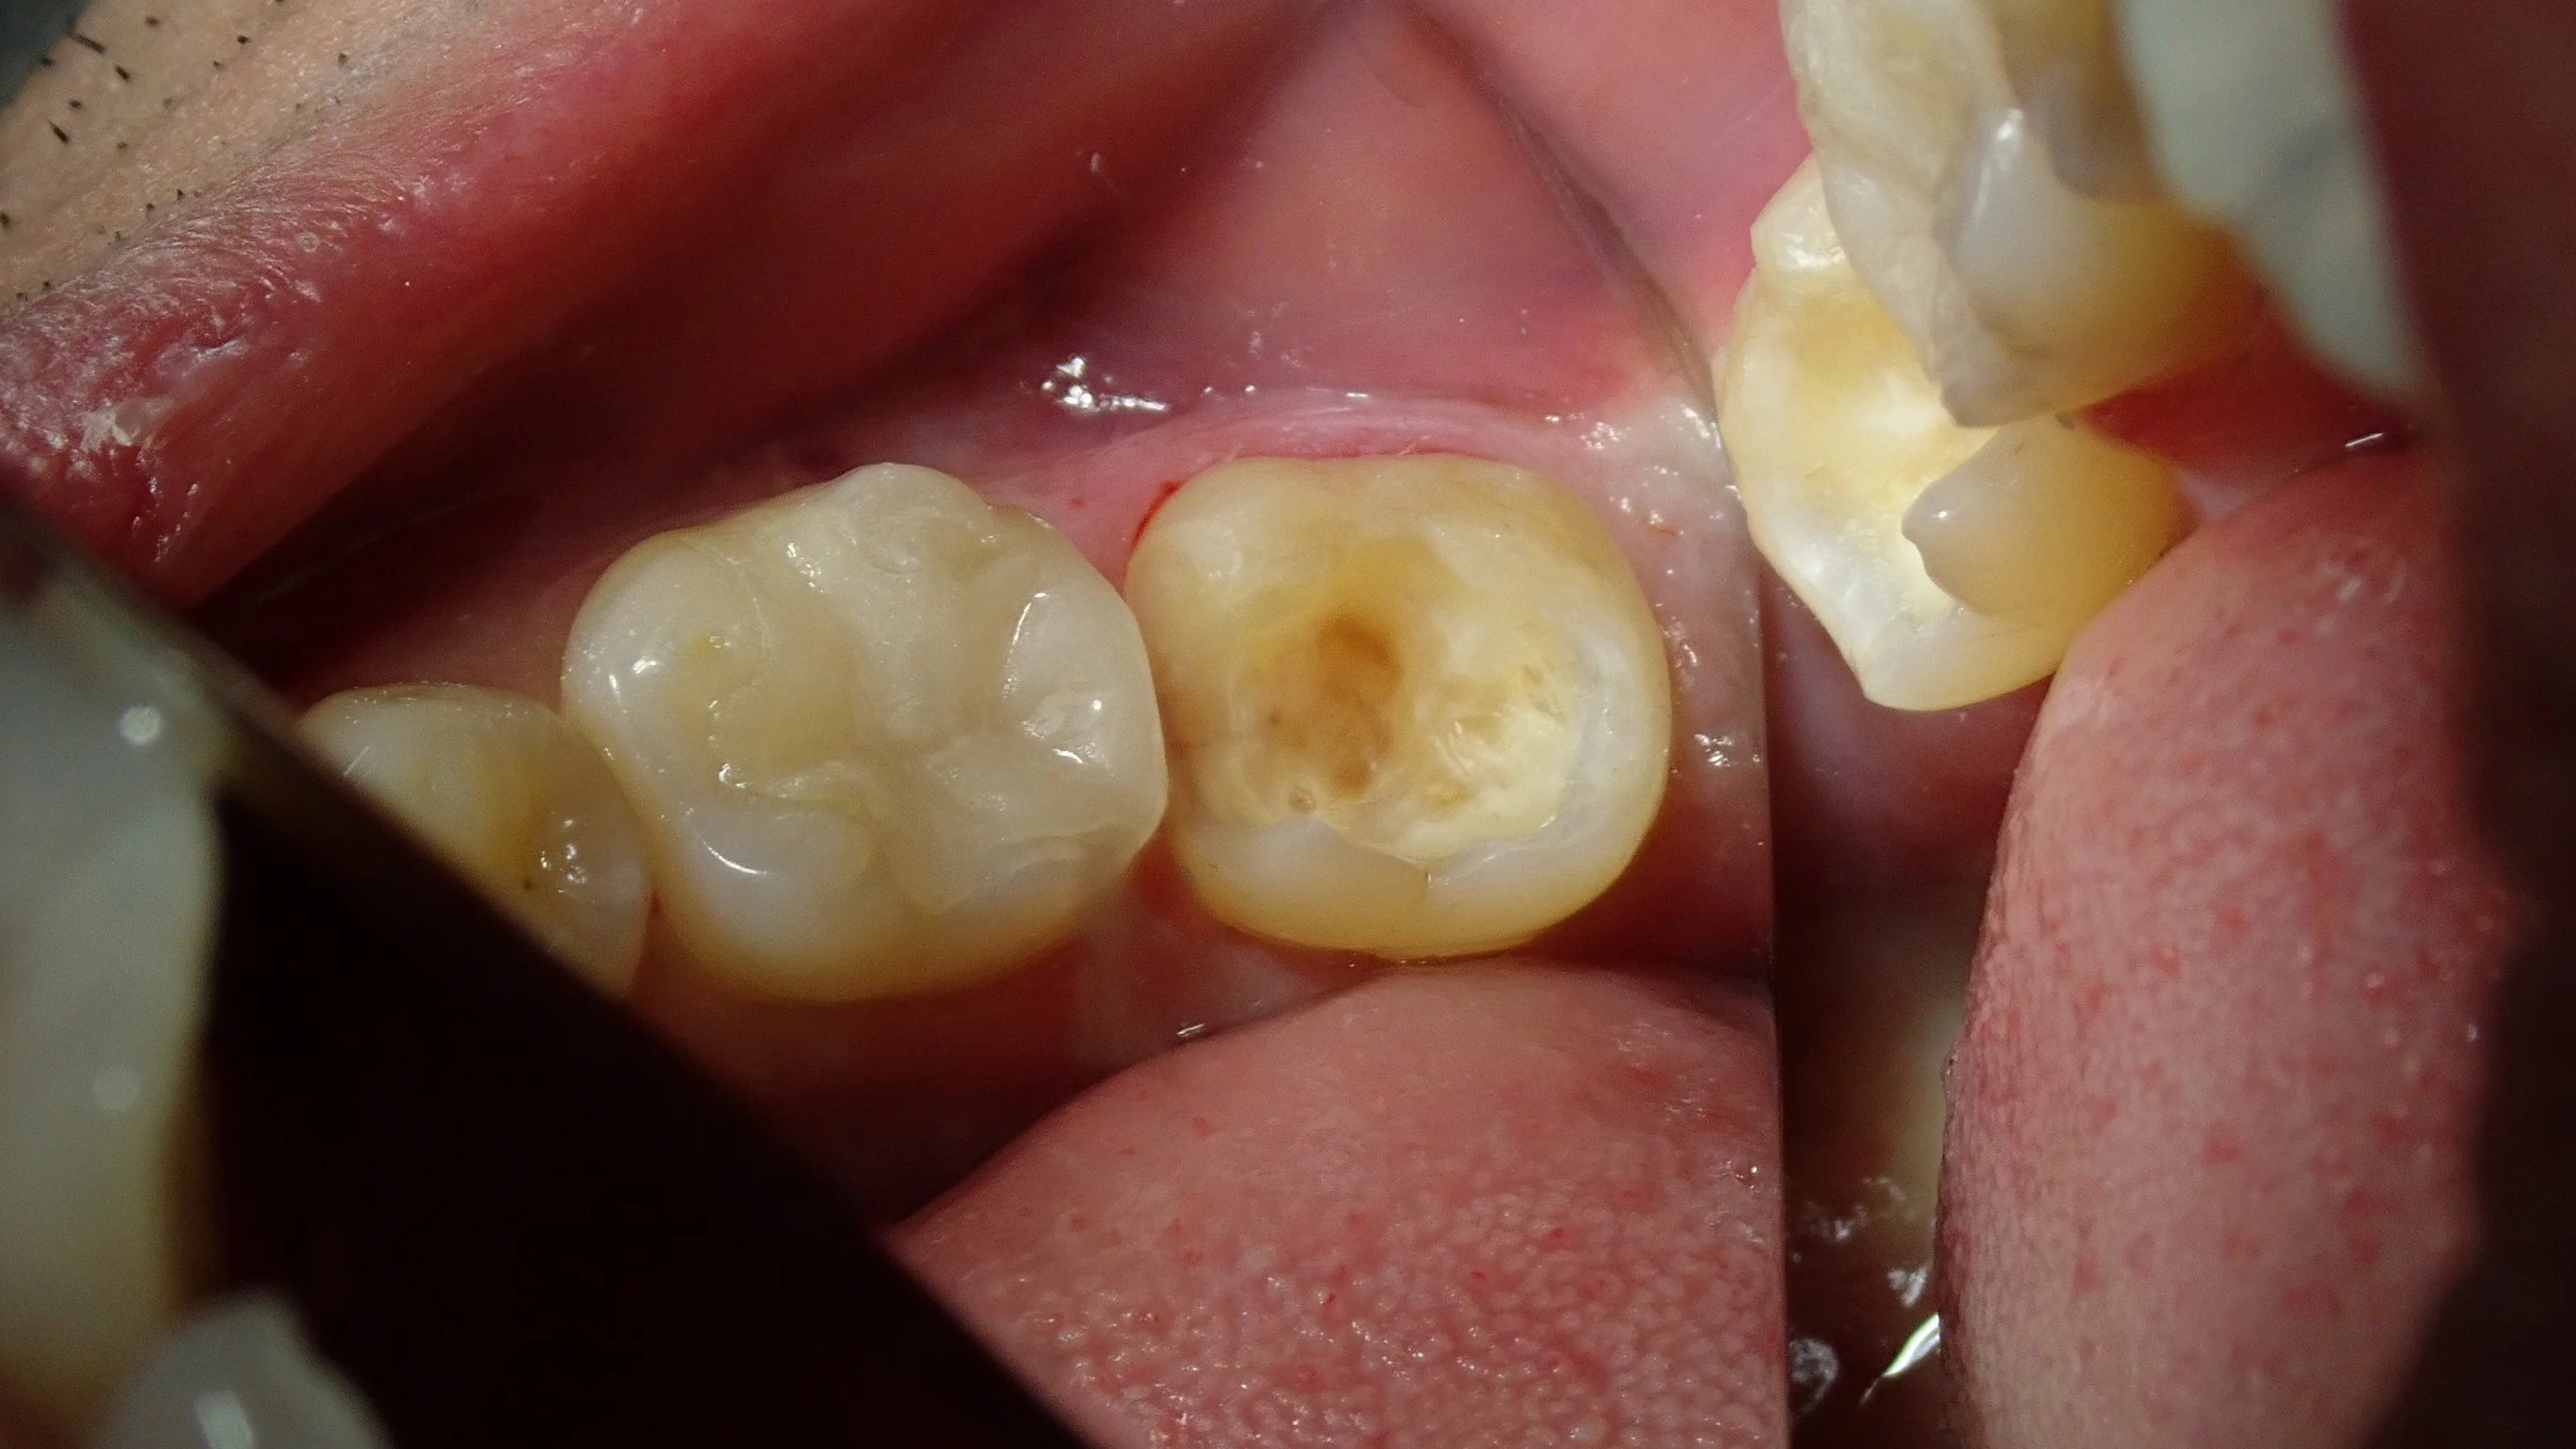

ちなみに、虫歯を取りきった後の写真がこちらです。

結構神経ギリギリになりました。

歯に色がついている所が残っていますが、ここは十分な硬さもあり、虫歯に汚染されている部分ではありません。

このまま詰めてしまっても全く問題はありません。

というより、ここまで取りきると神経が出てしまいかねないので、むしろここは取るとマズイ所ですね。